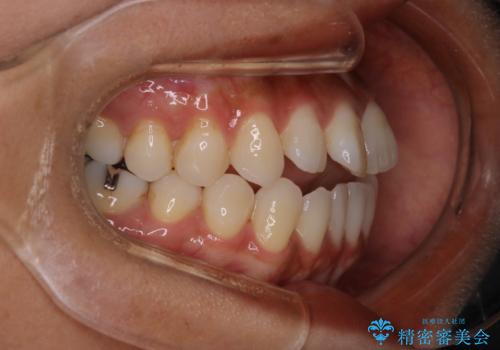

- 開咬を主訴に来院されました。前歯部に開咬、右側大臼歯部にクロスバイトが認められます。ワイヤー矯正の審美装置で治療し、ゴム掛けを行いながら噛み合わせを改善しました。

主訴である開咬と右側大臼歯部クロスバイトを改善でき、しっかりと噛むことができるようになりました。